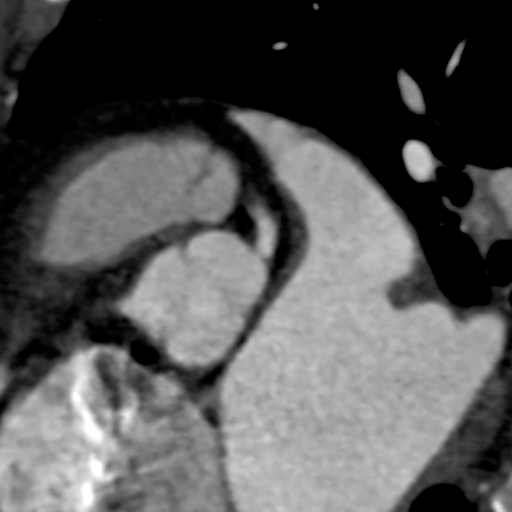

术中操作

球囊预扩

瓣膜初始定位

即刻超声评估示瓣周漏显著降低